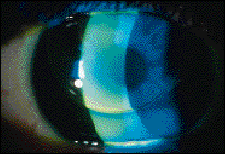

FIG. 1: Tangent Streak translating bifocal with proper seg height.